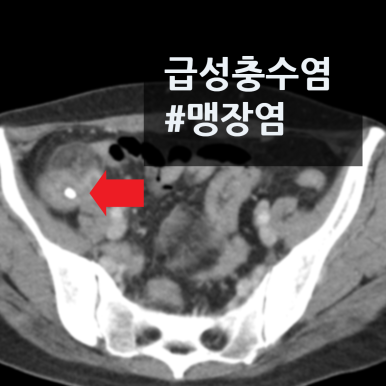

게실염, 충수염, 하복부통증 증상의 원인을 정확하고 신속하게 진단합니다.

게실염, 충수염, 하복부통증에 통해 관련 사례를 확인하실 수 있습니다.